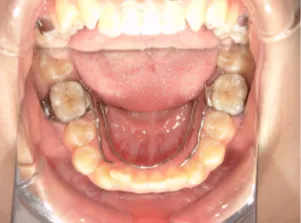

治療中③中1:非抜歯治療の診断で、上顎に歯の生えるスペースをつくるため上顎左右6をプレートで遠心移動し、隙間ができた時点

マルチブラケット法へ移行します

*マルチブラケット法移行前

*マルチブラケット法移行後